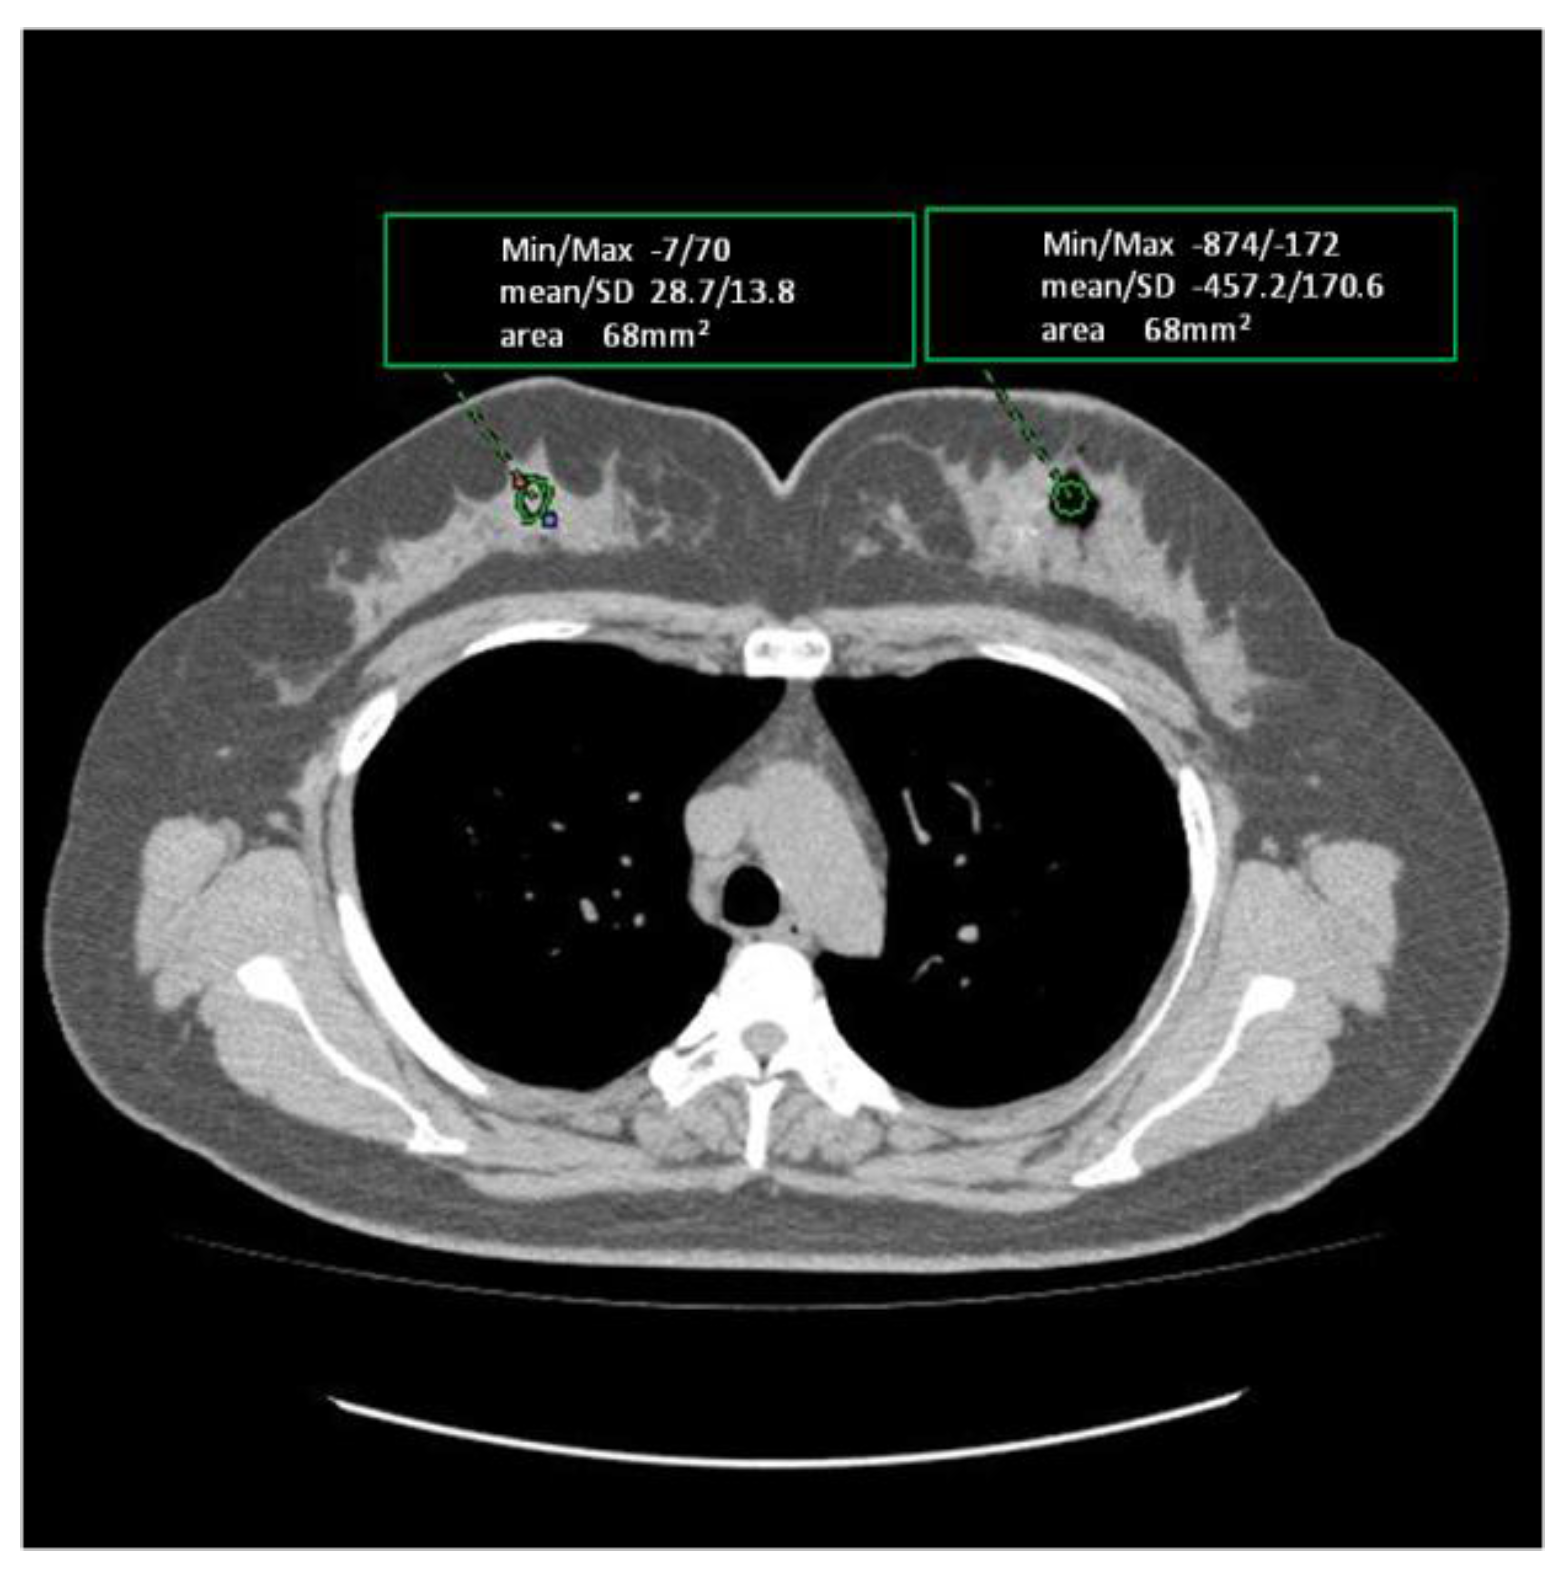

No, ultrasound is a powerful tool but may need support from tests like CT, MRI, or blood tests for accurate diagnosis.